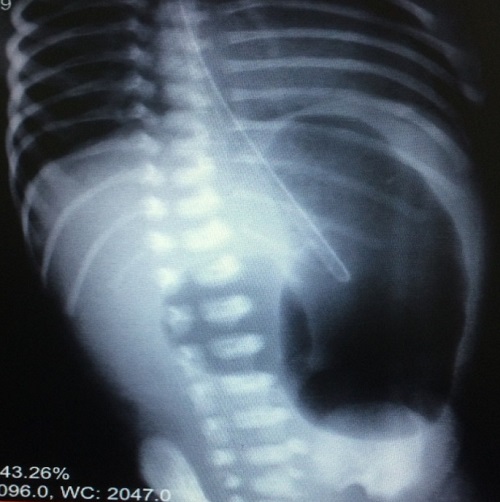

A 6-day-old female neonate developed signs of neonatal intestinal obstruction. She was a product of twin pregnancy with gestational age of 35 weeks. At birth, she underwent CPR in delivery room, and after intubation received one dose of surfactant. The other twin was normal. On the 4th day she was extubated but very next day developed bilious vomiting and was referred to our center. Thoraco-abdominal x-ray revealed double bubble sign in favor of duodenal obstruction (Fig. 1). Cardiology consultation revealed multiple cardiac anomalies. She underwent CT angiography later in the course of management which confirmed coarctation of the aorta. At laparotomy a distended stomach and huge cystic structure (communicating) attached to the greater curvature of stomach was found (Fig. 2). Further exploration revealed duodenal atresia type I with annular pancreas at 2nd part of the duodenum. The cyst excised and gastric wall repaired. Duodeno-duodenostomy was then carried out. Postoperative recovery was uneventful. The infant is doing well at six months follow-up.